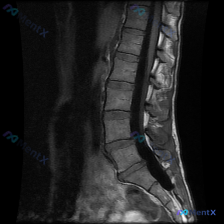

整理了一份腰椎影像资料,用户一开始问的是“这张图能看到脊柱侧弯吗?”。先说明一下,只有这份腰椎MRI T2加权矢状位序列。

先说说图里明确能看到的:

- 多个腰椎椎间盘信号普遍减低,考虑广泛脱水退变;

- L4/L5、L5/S1这些下腰段椎间盘后缘向椎管内突;

- L3/L4、L4/L5、L5/S1层面硬膜囊有受压,椎管前后径缩窄;

- 腰椎生理前凸还在,没看到明显滑脱、急性骨折、肿瘤破坏或脓肿这些红旗征象。